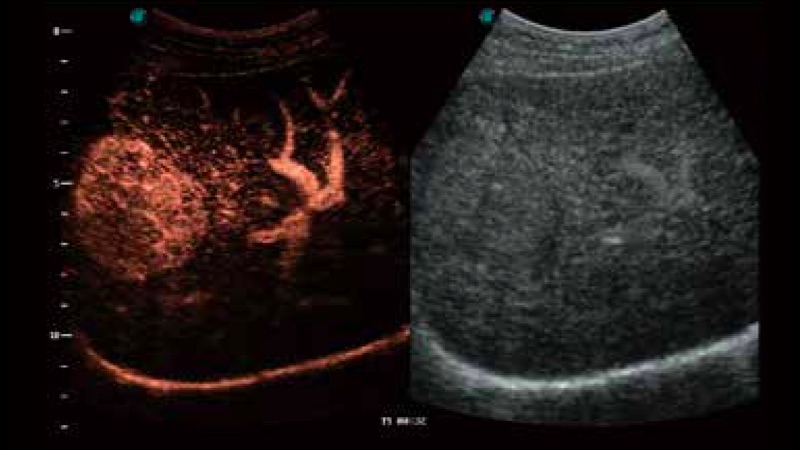

開立醫(yī)療通過不斷的技術(shù)創(chuàng)新,為大眾的生命健康提供持續(xù)關(guān)愛。P12 Plus采用全新一代超聲成像平臺,新平臺旨在將真實(shí)還原組織解剖結(jié)構(gòu)作為首要目標(biāo)。平臺采用全新集成化硬件模塊,搭載新一代芯片,系統(tǒng)性能得到大幅提升,為您的診斷提供了豐富的臨床信息。優(yōu)異的圖像表現(xiàn),豐富的探頭配置,全面的應(yīng)用功能,為您日常診斷提供了可靠的助手。

P12 Plus

彩色多普勒超聲診斷系統(tǒng)